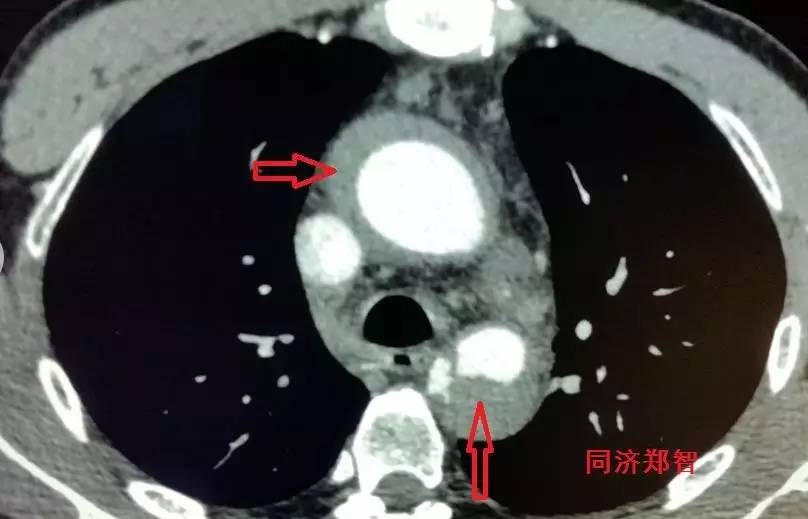

① Stanford B型 主动脉壁间血肿的CTA重建(图1),提示胸降主动脉以远的主动脉壁病变(红箭头所示)。

图1